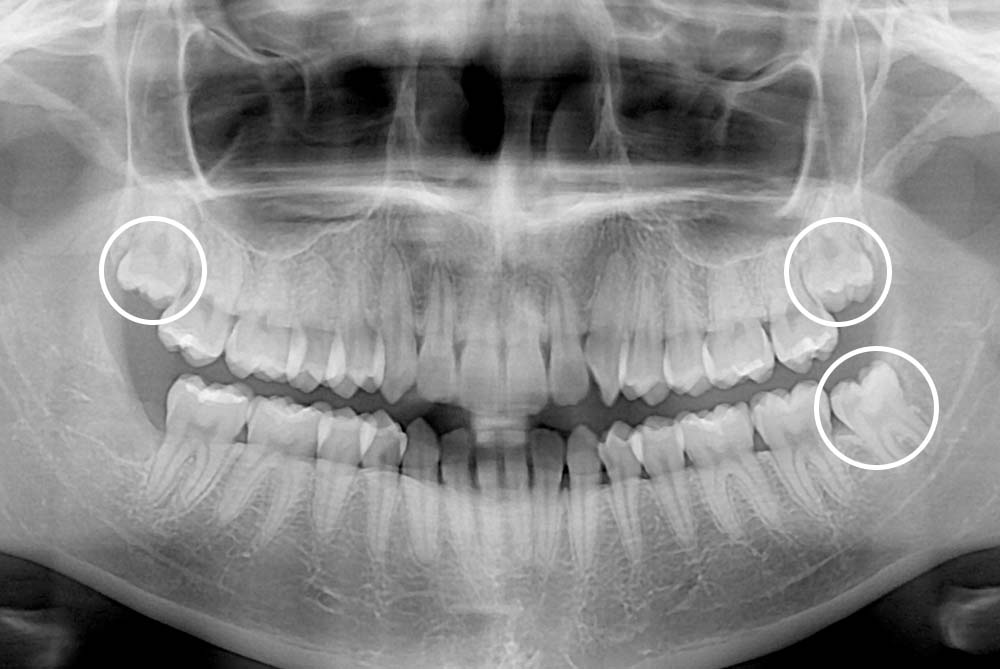

치료사례

세종치과의 진심 어린 치료는 결과로 말합니다.

실제 내원하신 환자분들의 치료 전·후 사례를 확인해보세요.

모든 치료사례 전후사진은 환자분의 동의하에 촬영되었습니다.

모든사진은 동일 환자분의 전후모습을 촬영하였으며, 사진의 밝기조절 외에 임의 수정이 없음을 알려드립니다.